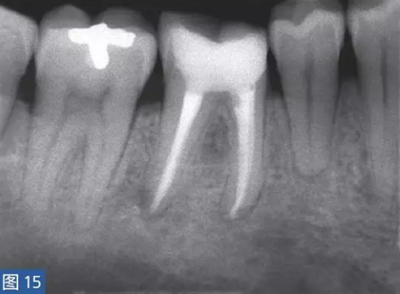

放射學檢查是診斷根尖周炎的一個重要工具。當然,也存在多種類似于牙髓源( endodonticorigin)病變的X 線透射和阻射病變,這其中包括例如外傷、異物反應(yīng)、埋伏的遷移殘根和良性或者惡性纖維骨性腫瘤。根尖周炎也可能擴散至鄰牙,這對應(yīng)著一個獨立的根尖周炎影像(圖14 和15)。為了獲得準確的診斷,還要進行臨床檢查,包括了解患者的癥狀及病史,并與放射學檢查結(jié)果進行比較。

圖14:鑒別診斷。第4 象限的術(shù)前影像(取自全景片的放大圖像)?;颊吒杏X在第IV象限區(qū)的牙齒存在大范圍的不適癥狀。放射學檢查顯示, 45-47 牙齒可見透影區(qū)。臨床檢查,觸診和叩診45-47 牙齒疼痛明顯。46 牙齒的牙髓電活力測試為陰性,47 和45 牙齒未顯示病理特征。

圖15:根管治療12 個月后的放射學檢查?;谂R床診斷,只有46 牙齒需要治療,因為它是根尖病變的主要病理原因.